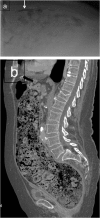

Emergency and trauma care produces a "perfect storm" for radiological errors: uncooperative patients, inadequate histories, time-critical decisions, concurrent tasks and often junior personnel working after hours in busy emergency departments. The main cause of diagnostic errors in the emergency department is the failure to correctly interpret radiographs, and the majority of diagnoses missed on radiographs are fractures. Missed diagnoses potentially have important consequences for patients, clinicians and radiologists. Radiologists play a pivotal role in the diagnostic assessment of polytrauma patients and of patients with non-traumatic craniothoracoabdominal emergencies, and key elements to reduce errors in the emergency setting are knowledge, experience and the correct application of imaging protocols. This article aims to highlight the definition and classification of errors in radiology, the causes of errors in emergency radiology and the spectrum of diagnostic errors in radiography, ultrasonography and CT in the emergency setting.